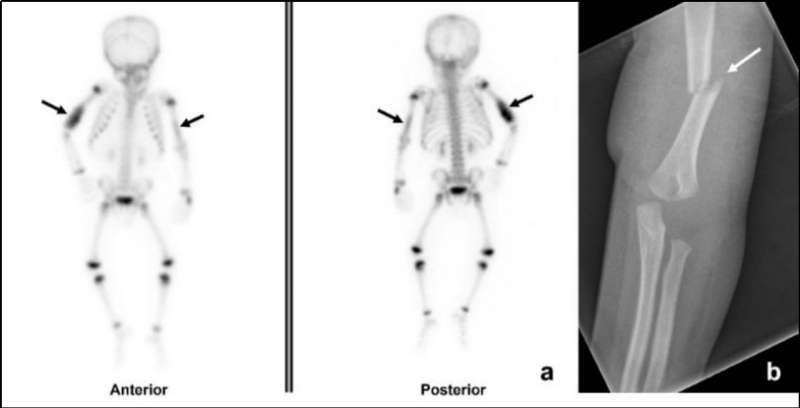

Cuando el estudio radiológico esquelético es normal o ambiguo y existe alta sospecha de maltrato, puede realizarse una gammagrafía ósea (como lo afirma el panel de expertos de American College of Radiology, ACR: “Indicado cuando la sospecha clínica de abuso sigue siendo alta y todavía es necesaria la documentación” )(15).

El centellograma óseo también puede realizarse como una alternativa a la seriada esquelética en niños entre 2 y 5 años, ya que la probabilidad de lesión metafisaria clásica es baja en este grupo de edad (Fig. 5). Conway et al. y otros, en un informe de dos estudios y una revisión de la literatura, concluyen que la gammagrafía esquelética es el mejor estudio complementario para la evaluación de la sospecha de abuso infantil(13). La gammagrafía puede identificar fracturas agudas de costillas que no son evidentes en las radiografías, pero es menos sensible en la detección de las fracturas metafisarias (Fig. 6) y fracturas de cráneo (13,16).

Habitualmente en nuestras instituciones el centellograma esquelético se realiza sin anestesia; se intenta privar antes al niño de sueño, indicándole a la persona cuidadora que lo haga conciliar el sueño inmediatamente antes de adquirir las imágenes. El estudio es de gran utilidad ya que los cambios metabólicos preceden a los anatómicos, visualizándose las fracturas aun cuando estas no presenten signos de reparación radiográfica, así como también la distribución y extensión de las lesiones. En nuestro caso fue útil al permitir identificar el compromiso mandibular no detectado en el examen físico ni radiológico inicial.